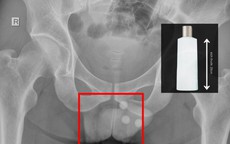

GĐXH - Ở tuổi 30, anh Hoàng được chẩn đoán vô sinh, khả năng có con tự nhiên rất thấp do trong mẫu tinh dịch chỉ ghi nhận 1–2 tinh trùng. Nhờ được bác sĩ xây dựng phác đồ điều trị phù hợp, cơ hội làm cha của anh đã được giữ lại.